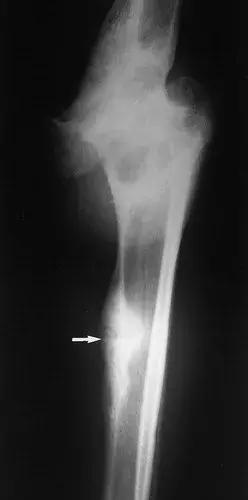

图8:50岁男性,三期梅毒,膝关节的神经性骨关节病。X线片显示胫骨平台受到冲击和破碎(黑色箭头)。在小腿内侧(白色箭头)软组织内可见骨碎片,远离关节。 (来自ACR学习档案,MSK案例234.)